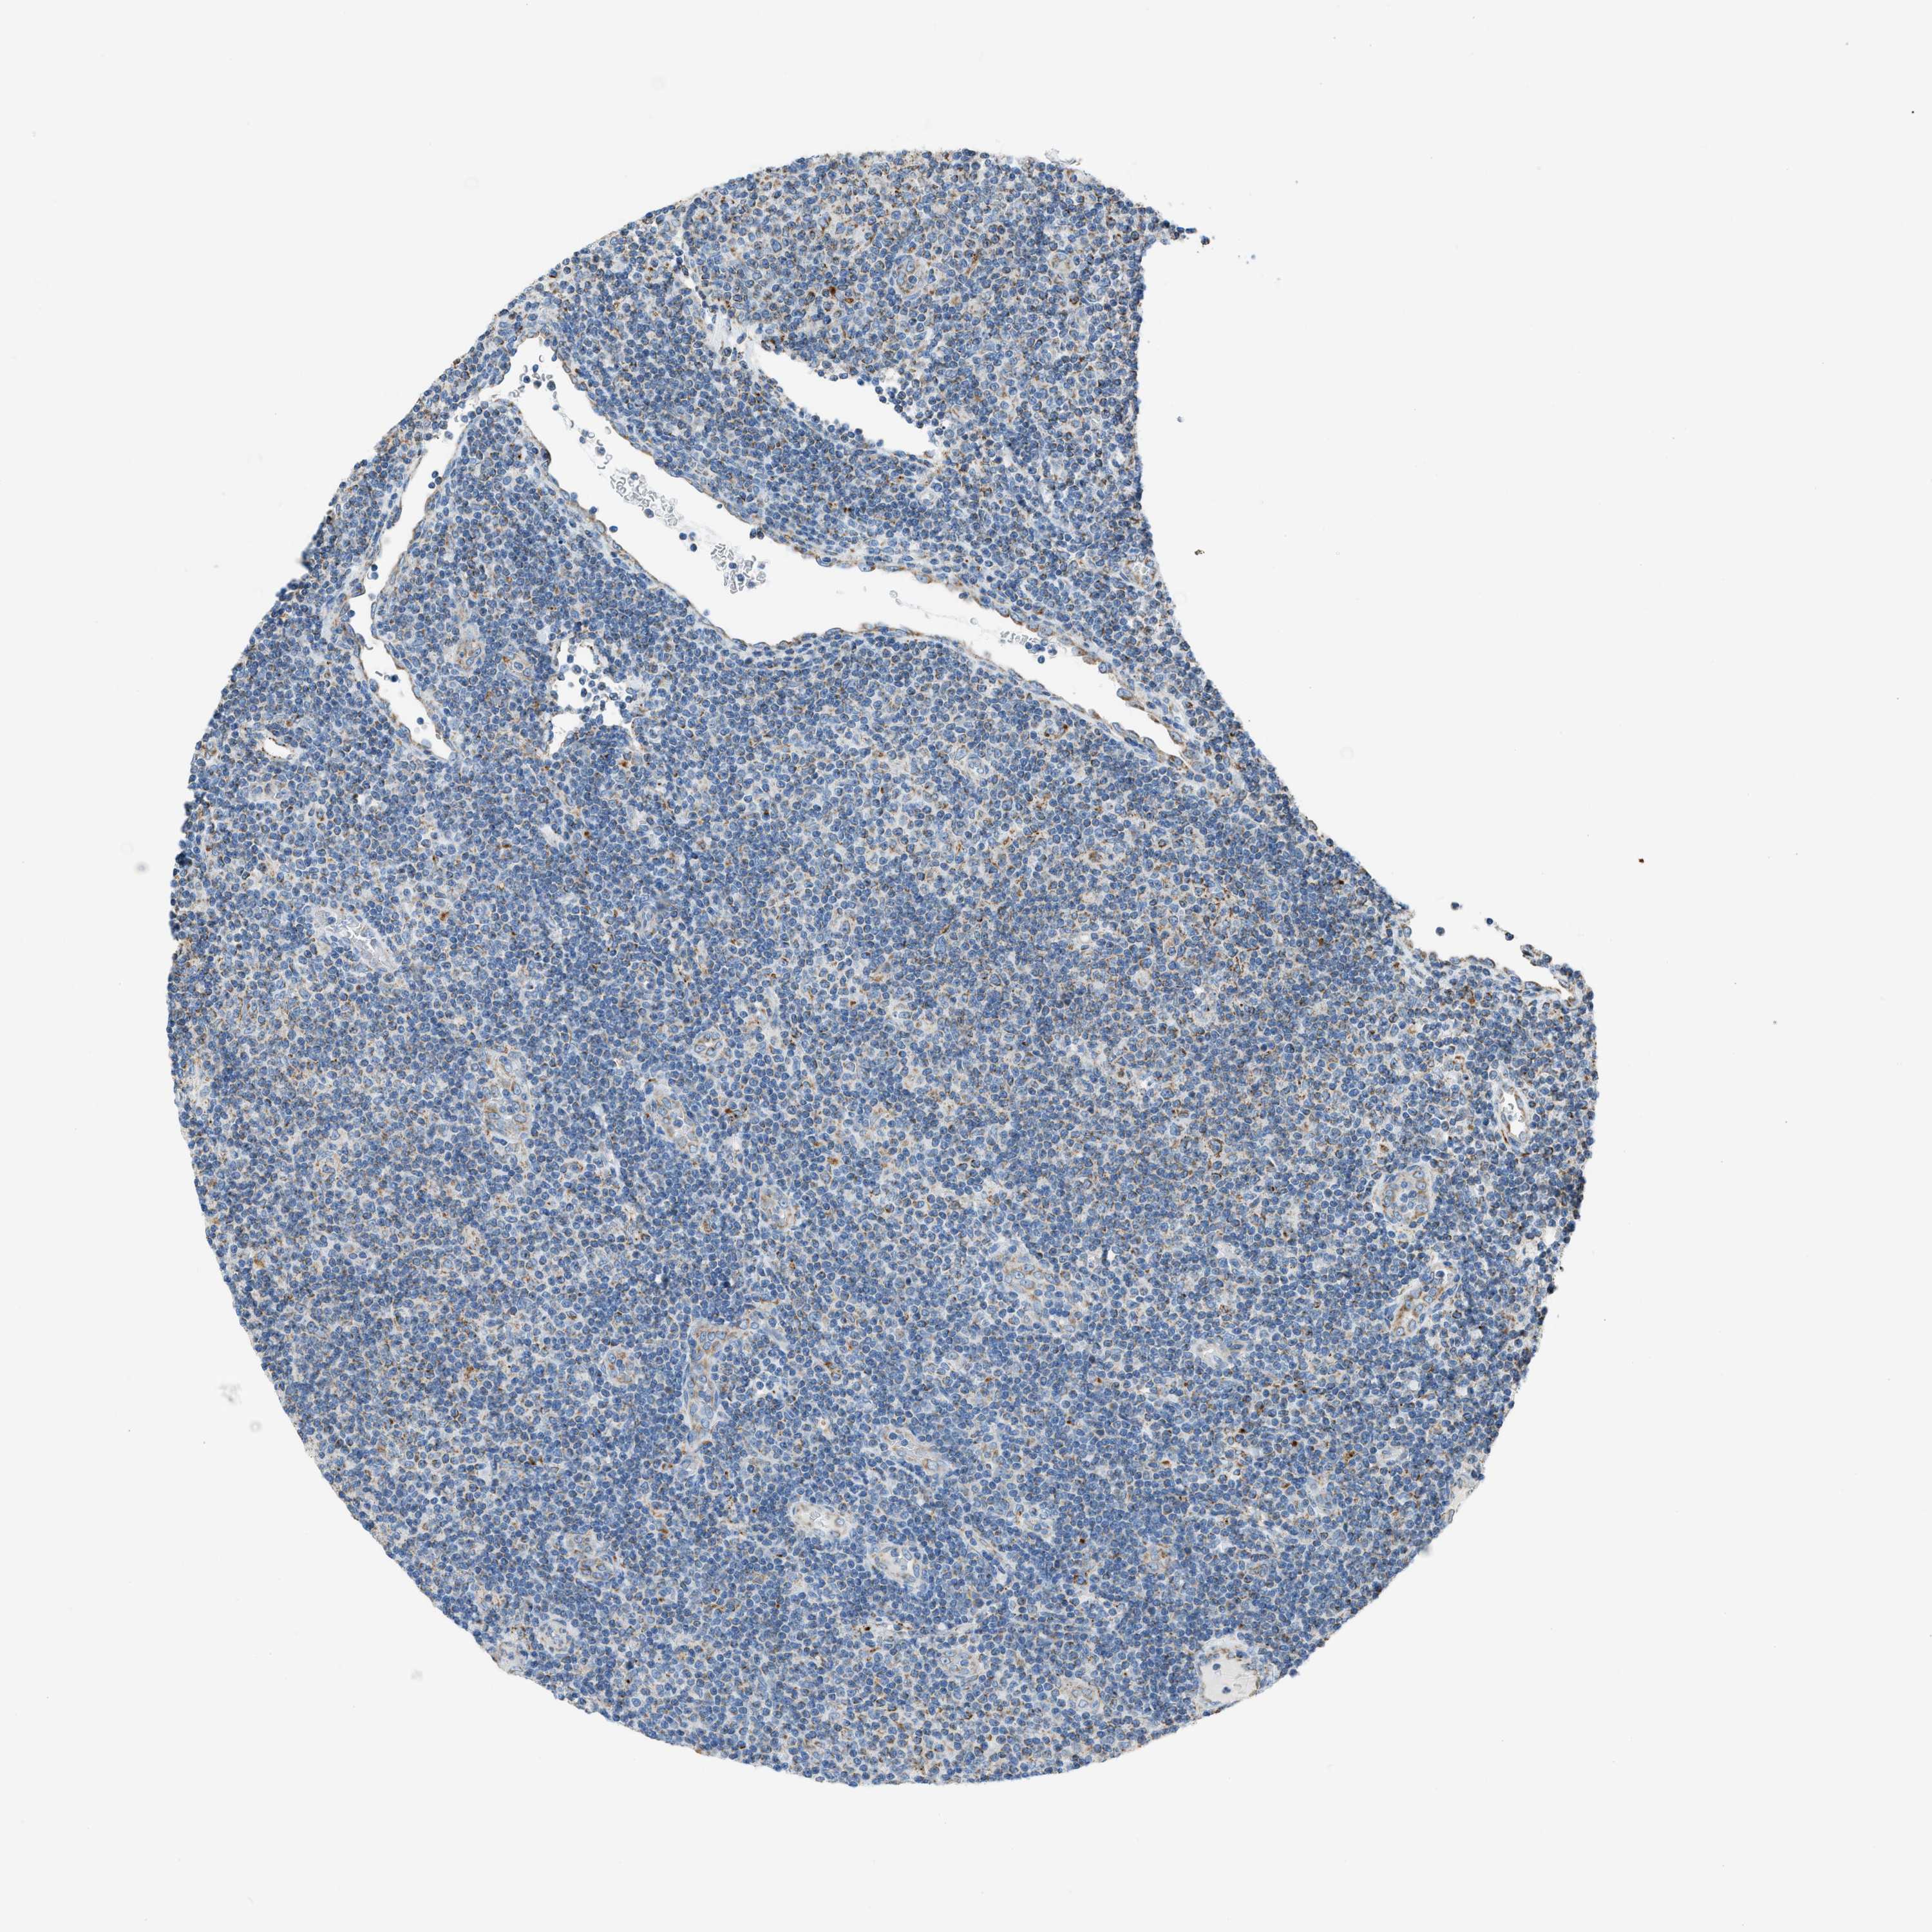

CANCER LYMPHOMA Show tissue menu

LYMPHOMA - Protein expressioni

A mouse-over function shows sample information and annotation data. Click on an image to view it in a full screen mode. Samples can be filtered based on level of antibody staining by selecting one or several of the following categories: high, medium, low and not detected. The assay and annotation is described here.

Antibody stainingi

Antibody staining in the annotated cell types in the current human tissue is reported as not detected, low, medium, or high, based on conventional immunohistochemistry profiling in selected tissues. This score is based on the combination of the staining intensity and fraction of stained cells.

Each image is clickable and will lead to virtual microscopy that enables deeper exploration of all samples and also displays staining intensity scores, fraction scores and subcellular localization as well as patient and tissue information for each sample.

Antibody HPA016552

Staining

High

Medium

Low

Not detected

Intensity

Strong

Moderate

Weak

Negative

Quantity

>75%

75%-25%

<25%

None

Location

Nuclear

Cytoplasmic/membranous

Cytoplasmic/membranous,nuclear

Hodgkin's disease, NOS

Malignant lymphoma, non-Hodgkin's type, High grade

Malignant lymphoma, non-Hodgkin's type, Low grade